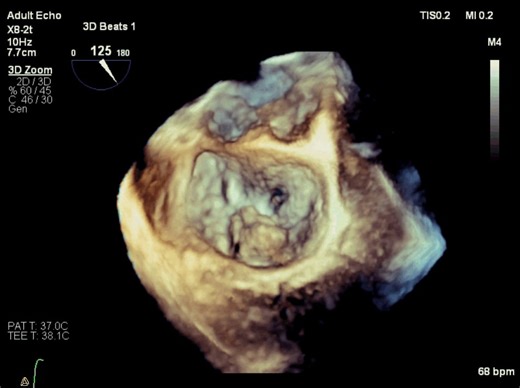

10K views · 13 reactions | Mitral Regurgitation - Carpentier Functional Classification Type I - Normal leaflet motion Type II - Excess leaflet motion (leaflet prolapse) Type III -

Abdallah Othman. . Mitral Regurgitation - Carpentier Functional Classification Type I - Normal leaflet motion Type II - Excess leaflet motion (leaflet prolapse) Type III - Restricted leaflet motion Type Illa - Restricted leaflet motion during diastole and systole; Type 111b - Restricted leaflet motion predominantly during systole #Mitral # ...

Modified Carpentier functional classification of mitral valve disease

Carpentier Nomenclature of Mitral Leaflet Scallops

Type I Carpentier Classification in Mitral Regurgitation (MR) (Transes

Type 2 Carpentier Classification in Mitral Regurgitation (MR) (Transes

Carpentier's functional classification of mitral valve dysfunction

Carpentier classification